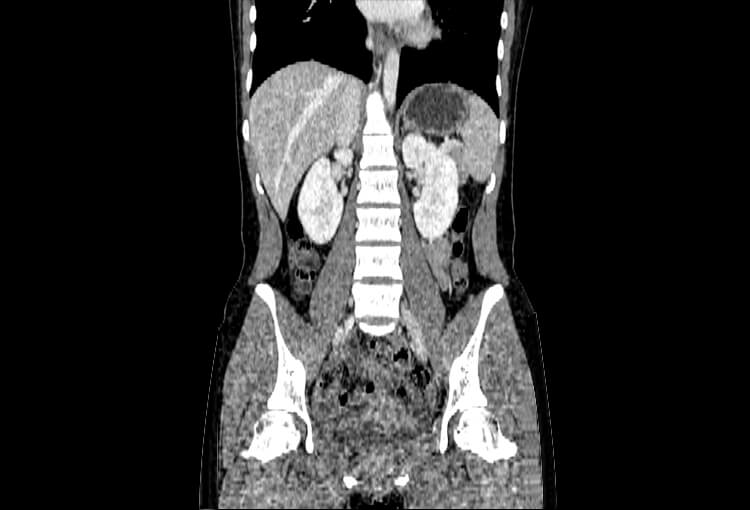

120 kV / 20 mAs / 1 mm

Before FBP (Noise 189) VS After ClariCT.AI (Noise 46) 76% Denoising